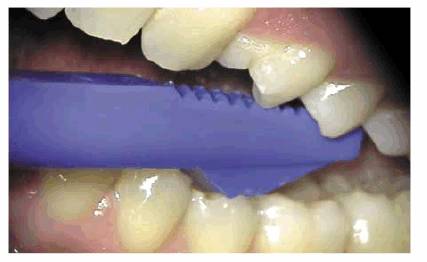

Bite Test

Every time that the patient's complaint is sensitivity to biting and/or

chewing, it is important to investigate further which tooth and, more

importantly, which part of it are sensitive to biting pressure. This is to

distinguish between vertical crown/root fractures and periapical pathosis. A

very convenient instrument for this investigation is the Tooth Slooth

(Professional Results,

A plastic saliva ejector may be used as an alternative instrument for this test

(Figure 19-23

Figure 19-21: Tooth Slooths, two sizes.

Figure 19-22A: Bite test with Tooth Slooth (Professional Results) checking DB cusp of mandibular molar.

Figure 19-22B: Bite test with smaller-sized (blue) Tooth Slooth.

Figure 19-23: Plastic saliva ejector is useful in bite testing the entire tooth rather than an individual cusp.